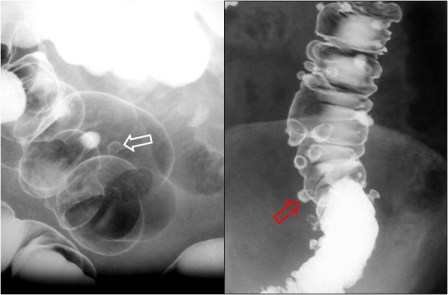

SIGNO DEL PSEUDOTUMOR

En la radiografía simple de abdomen, cuando un asa intestinal está obstruida por un vólvulo se llena de líquido y produce una falsa imagen de masa con densidad de partes blandas (flechas) que no debe confundirse con un tumor.

Este signo debe diferenciarse de las asas rellenas de líquido en la obstrucción mecánica simple. En la obstrucción en asa cerrada, la presencia del signo del pseudotumor indica que un asa intestinal se encuentra fija y permanece en la misma posición en todas las proyecciones.

En la imagen, pseudomasa causada por asas distendidas, con líquido, en la obstrucción intestinal.